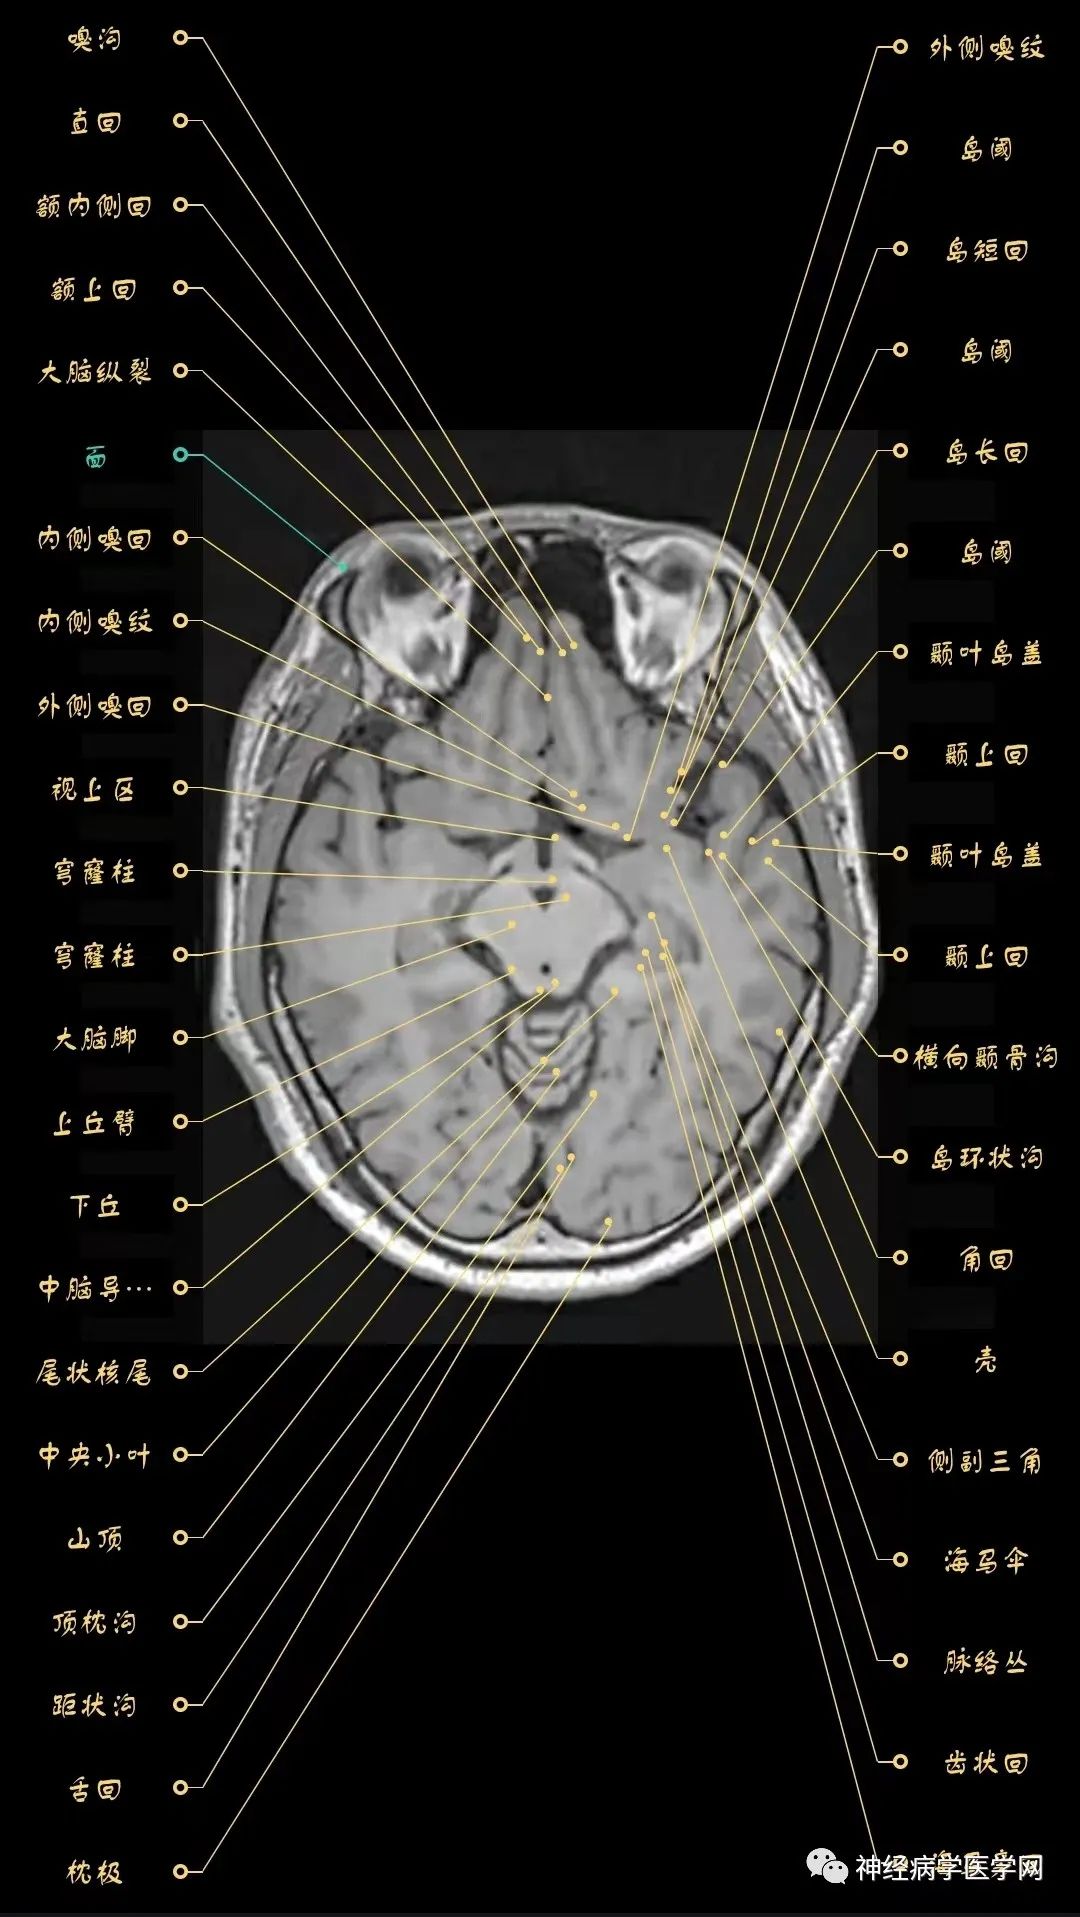

高清颅脑mri最全轴位影像解剖人手一册

脑mri必备丨最详细的脑mri解剖_影像诊断中心

神经影像解剖系列颅脑mri超详细三维标注震撼来袭